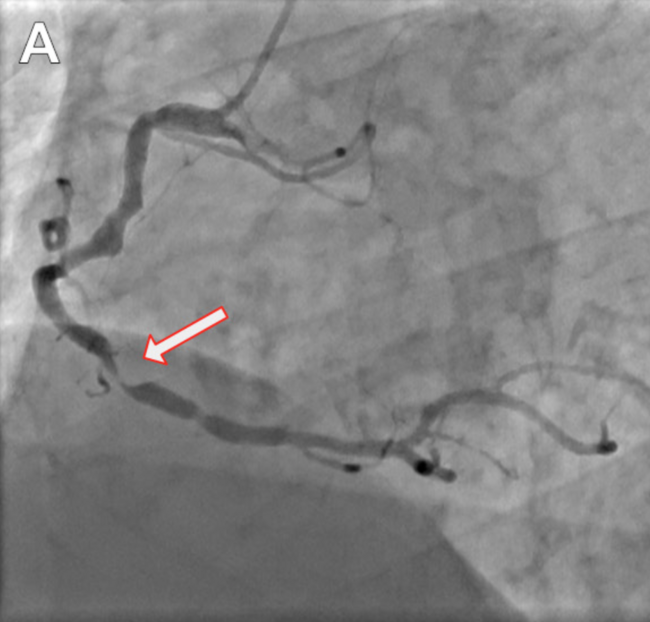

A 47-year-old male lifelong smoker underwent percutaneous coronary intervention (PCI) to the distal segment of an ectatic right coronary artery (RCA) in the context of non–ST-elevation myocardial infarction (NSTEMI) (Figure 1A and Video 1). The procedure was intravascular ultrasound guided using an Amplatz Left 1 guide and Sion Blue wire (Asahi Intecc). After lesion preparation with semicompliant balloons, a Synergy 4 x 48-mm coronary stent (Boston Scientific) was delivered with support of a 6-Fr guide-catheter extension and optimized using 4.5 x 15-mm and 5.0 x 8-mm noncompliant balloons. Upon retrieval of the 5.0-mm balloon, the distal part detached from the shaft in the proximal RCA, leading to acute vessel closure, chest pain, and inferior ST-segment elevation (Figure 1B). With the detached balloon shaft partially lodged in the catheter tip, a 2 x 12-mm balloon was advanced in parallel and inflated at 18 atm to trap the detached shaft in the guide (Figure 1C and Video 1). The entire system was withdrawn, restoring antegrade flow. Upon retrieval, the device detached in the distal radial artery and had to be retrieved using a 15-mm GooseNeck snare (ev3) (Figures 1D-1F). A subsequent angiogram demonstrated a patent RCA and no evidence of dissection.